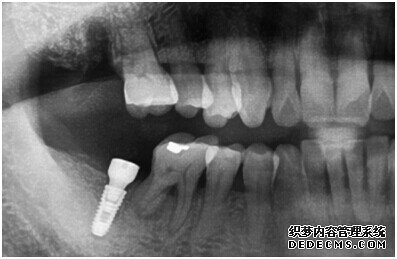

种植体成功植入后的CT效果图

整个种植牙完成后的效果图

种植牙整个过程完成后,刘女士非常满意自己的牙齿,并且表示以后一定会遵照医生的嘱咐好好注意自己的口腔健康,每晚一定会好好刷牙,饭后漱口,当然也会注意保护这颗种植牙!